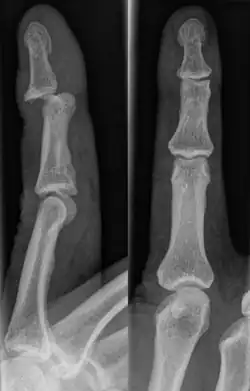

There are a variety of possible signs indicating a jammed finger. These depend on the severity of the injury.[3] They may include swelling, reduced joint flexibility, pain, tenderness, and joint deformity.[1] There may also be discoloration of the skin due to bruising. These symptoms usually persist for a few weeks.[3] In some cases, the damage and its effects can last for years.[4] Initial signs of a dislocation include abnormal bumps or projections at the joint. There may also be an audible popping noise when the injury occurs.[5] Fractures are indicated by abnormal protrusions along the bone,[6] where the bone itself appears split or twisted.

A jammed finger can generally be diagnosed by a physical examination. Bone or joint deformity may indicate potential dislocations or fractures.[6] The basic structure of the finger includes three bones with joints in between each.[9] The joint closest to the tip is the distal interphalangeal (DIP) joint. The next joint, moving closer to the hand, is the proximal interphalangeal (PIP) joint. The thumb differs by only having two bones and one interphalangeal joint.[10]

The injured finger may be examined to determine where the pain is worst.[3] If the finger is sprained or dislocated, pain will be worse at the joint rather than the bone.[3] Due to the risk of dislocations or fractures, X-rays should be conducted prior to testing joint stability. This allows for prior detection of a dislocation or fracture.[3] It is recommended that a variety of views (lateral, oblique, and anteroposterior) are observed.[3] In extremely painful cases, a digital nerve block may be done to better assess the finger. This is where anesthetic is injected to either side of the base of the affected finger to reduce pain.[3]

Fractures

Fractures are instances where the bone's structural integrity has been compromised.[20] If a jammed finger produces a fracture, pain will be greatest at the bone as opposed to the joint.[2] There may also be visual deformation of the bone itself.[6] As with any skeletal injury, an x-ray can be conducted to verify the presence of a fracture.[1] The distal phalanx is especially vulnerable to avulsion fractures.[1] These avulsion fractures are common following a first time dislocation of the DIP.[1]